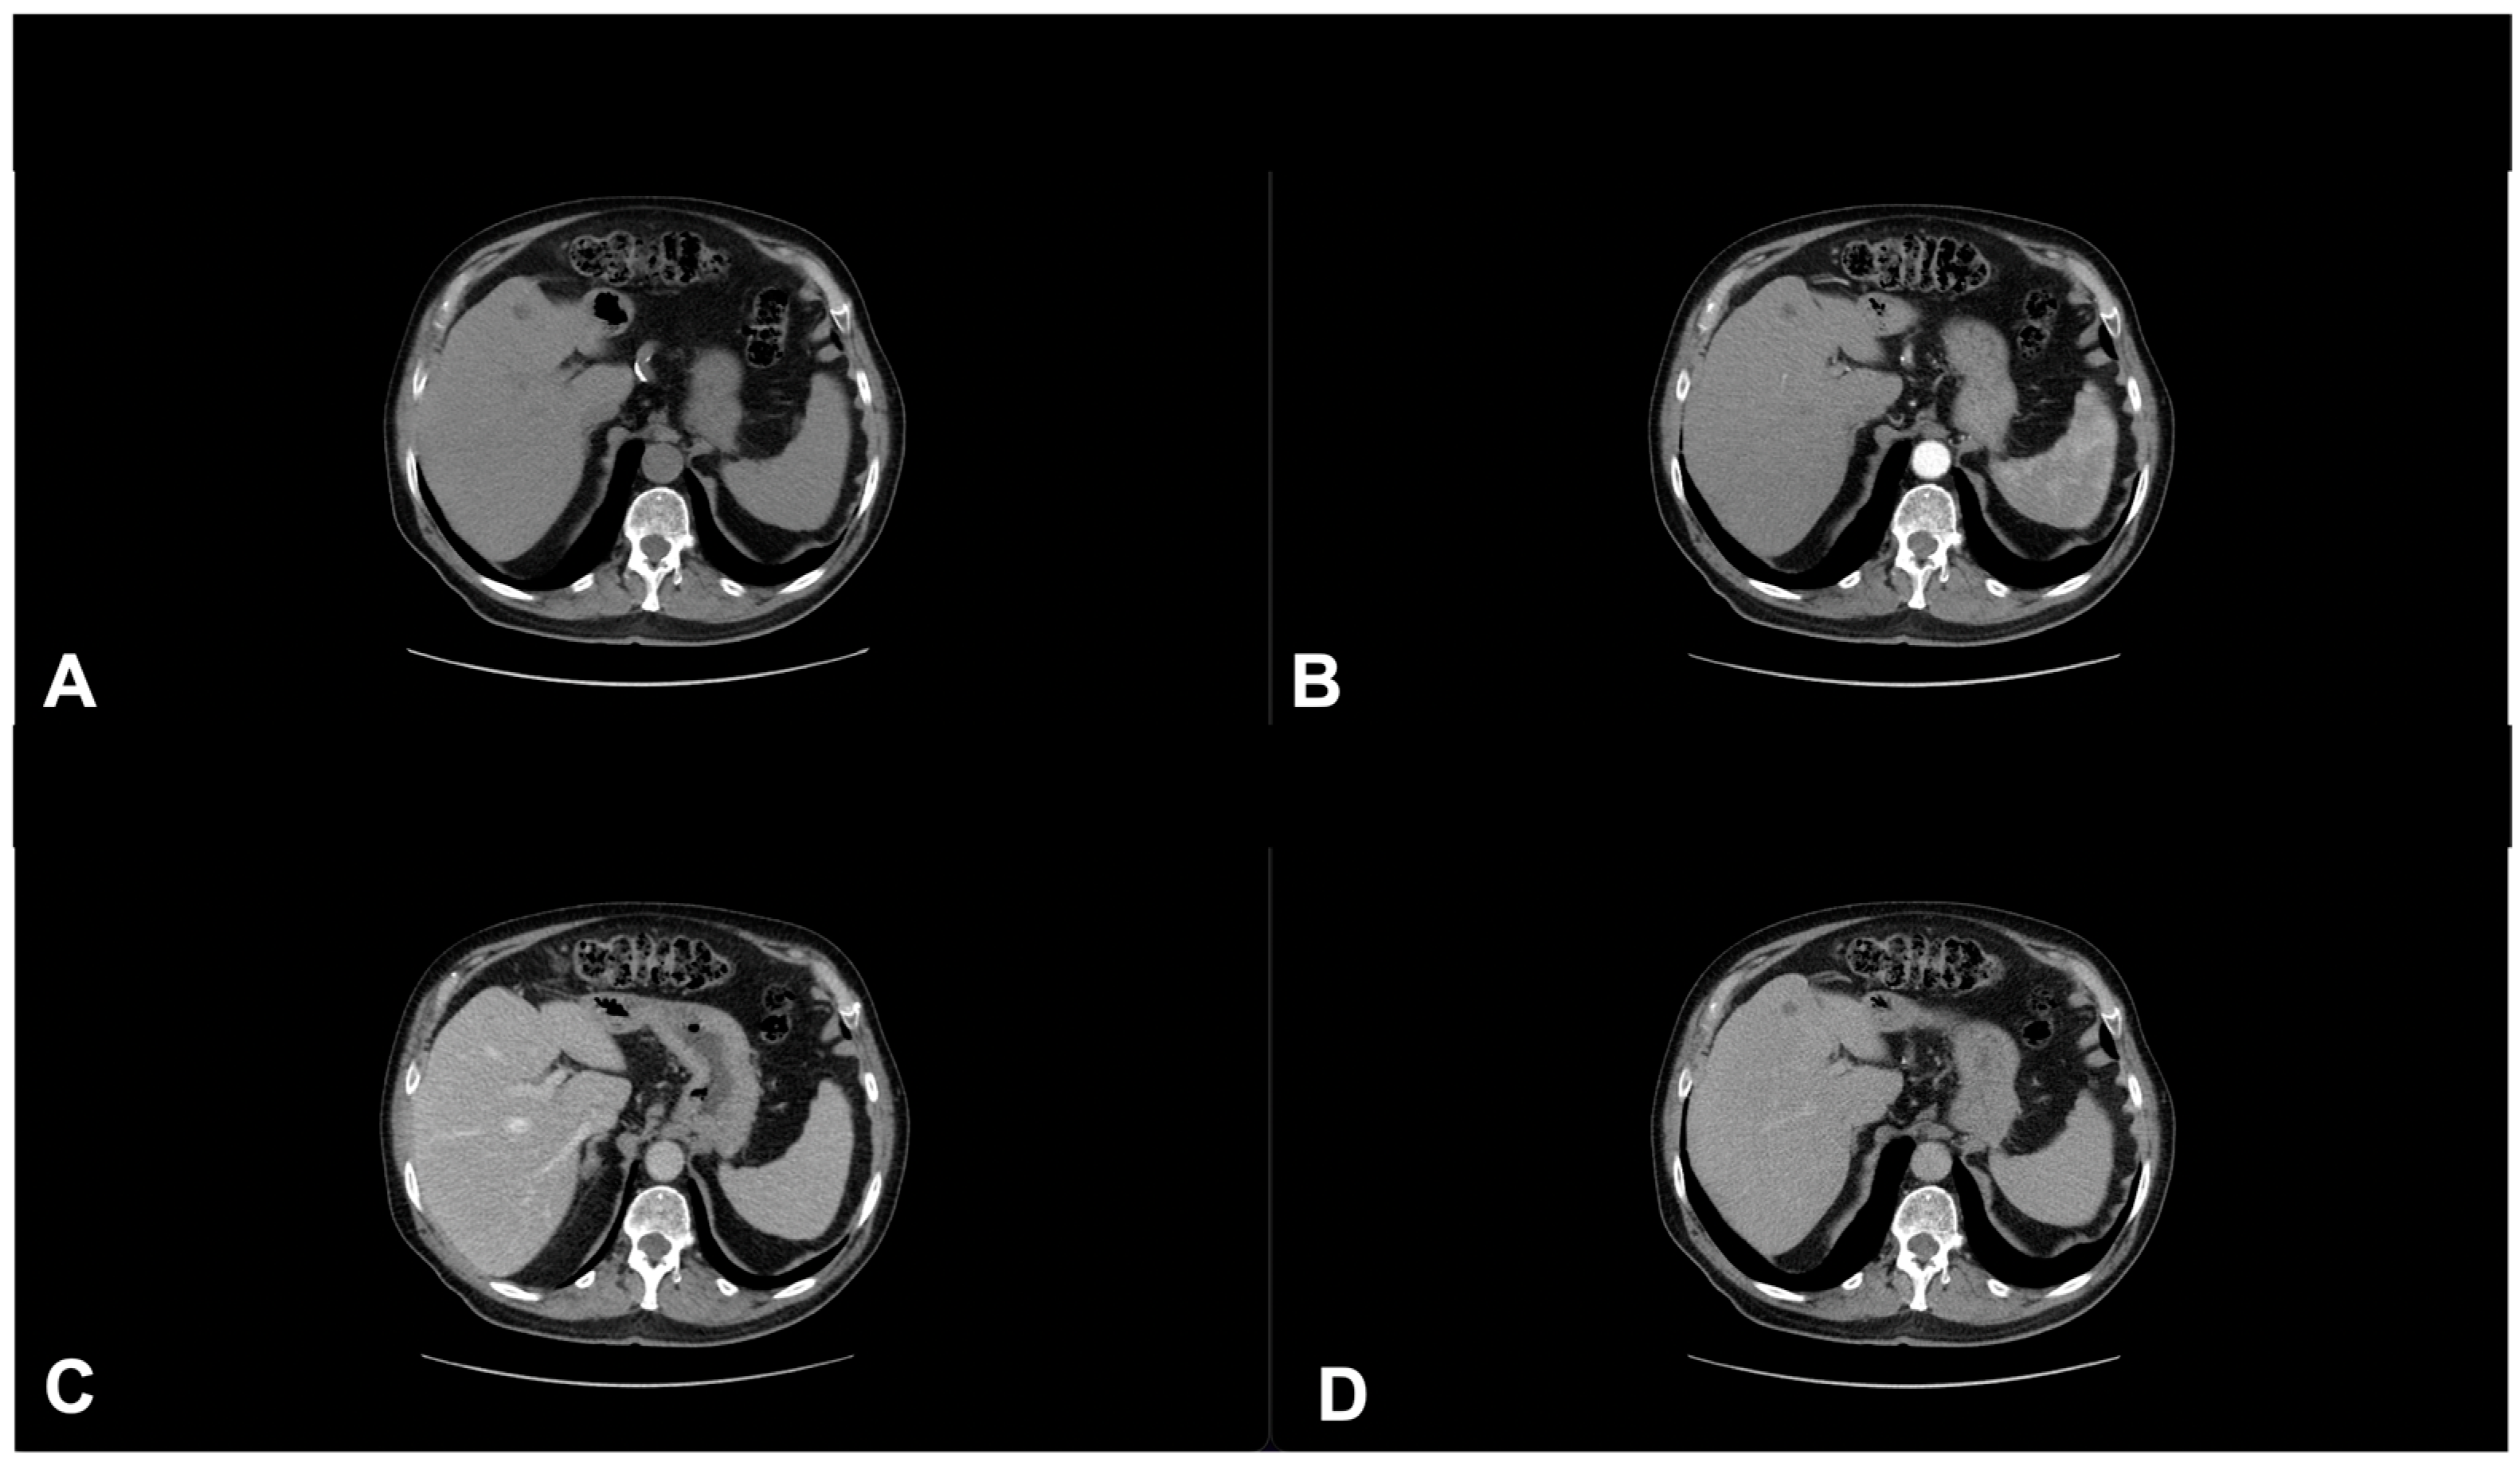

2. Diagnostic Imaging and Non-Melanoma Skin Cancer

3. Diagnostic Tools and Non-Melanoma: Staging and Surveillance

4. Follow-Up and Surveillance: Time